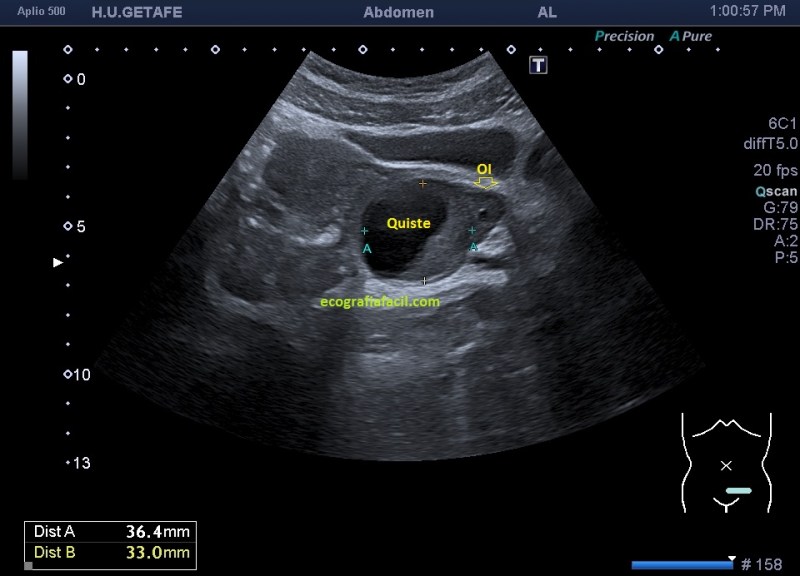

Vamos al ovario izquierdo:

En la imagen 7 ves la lesión que te he contado antes, circunscrita y medida, se demuestra que pertenece al ovario izquierdo, con un folículo diminuto y anecoico, que puedes verlo señalado por la flecha amarilla y hueca y dentro de esta estructura, la lesión, de aspecto quístico con contenido ecogénico.

En la imagen 8, medidas y volumen del quiste, que solo él, es siete veces mayor que ovario derecho.